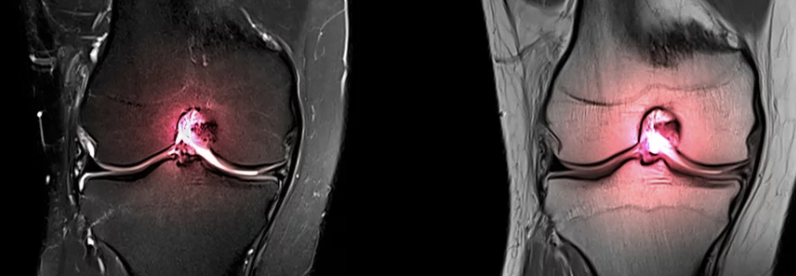

무릎 연골은 뼈를 보호하고 부드러운 움직임을 가능하게 하는 중요한 조직입니다. 하지만 나이, 운동, 체중, 질병 등의 영향으로 손상될 수 있으며, 이는 만성적인 무릎 통증, 붓기, 움직임 제한 등의 증상을 유발합니다. 심각한 경우 일상생활에도 지장을 줄 수 있으며, 삶의 질을 크게 떨어뜨릴 수 있습니다. 무릎 연골 손상 치료에는 다양한 방법이 있지만, 손상 정도가 심한 경우 수술이 필요할 수 있습니다. 무릎 연골 수술은 손상된 연골을 복구하거나 교체하여 통증을 완화하고 기능을 회복시키는 치료 방법입니다.